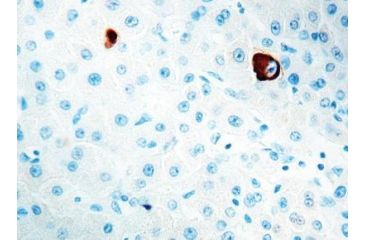

HBsAg. Clone number 3E7, This antibody stains the cytoplasm of antigen-positive liver cells in patients with Type B viral hepatitis. This antibody reacts with the ?a? determinant present on the HBsAg subtypes ayw1, ayw2, ayw3, ayw4, ayr, adw2, adw4 and adr. It does not react with normal tissues.